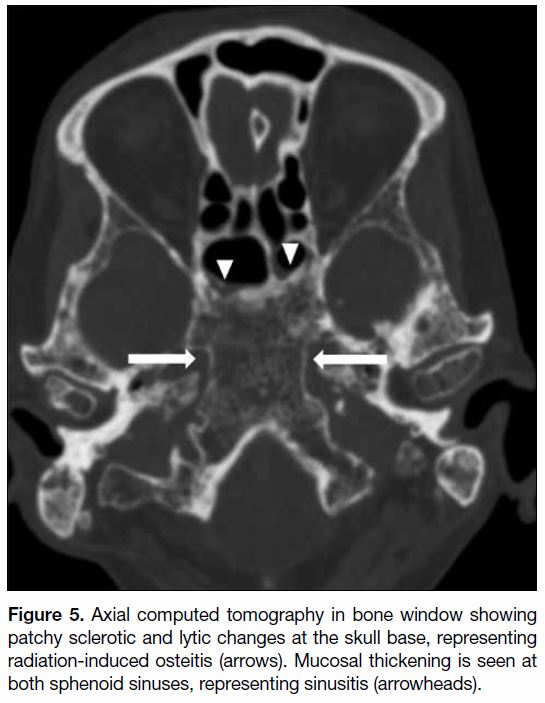

Radiation-induced osteitis

Radiation-induced osteitis is commonly asymptomatic

and involves the sphenoid bone at the skull base and upper

cervical spine. Radiation-induced fatty replacement of marrow is the most common osseous imaging

abnormality in post-irradiation patients, although initial

imaging may be normal. On computed tomography,

a mottled appearance of the skull base with mixed

patchy sclerosis and lucency and coarsened trabeculum

can be observed (Figure 5).[1] Further progression to

osteoradionecrosis with osseous changes can be seen in

some cases and will be further discussed later on.

Figure 5. Axial computed tomography in bone window showing

patchy sclerotic and lytic changes at the skull base, representing

radiation-induced osteitis (arrows). Mucosal thickening is seen at

both sphenoid sinuses, representing sinusitis (arrowheads).